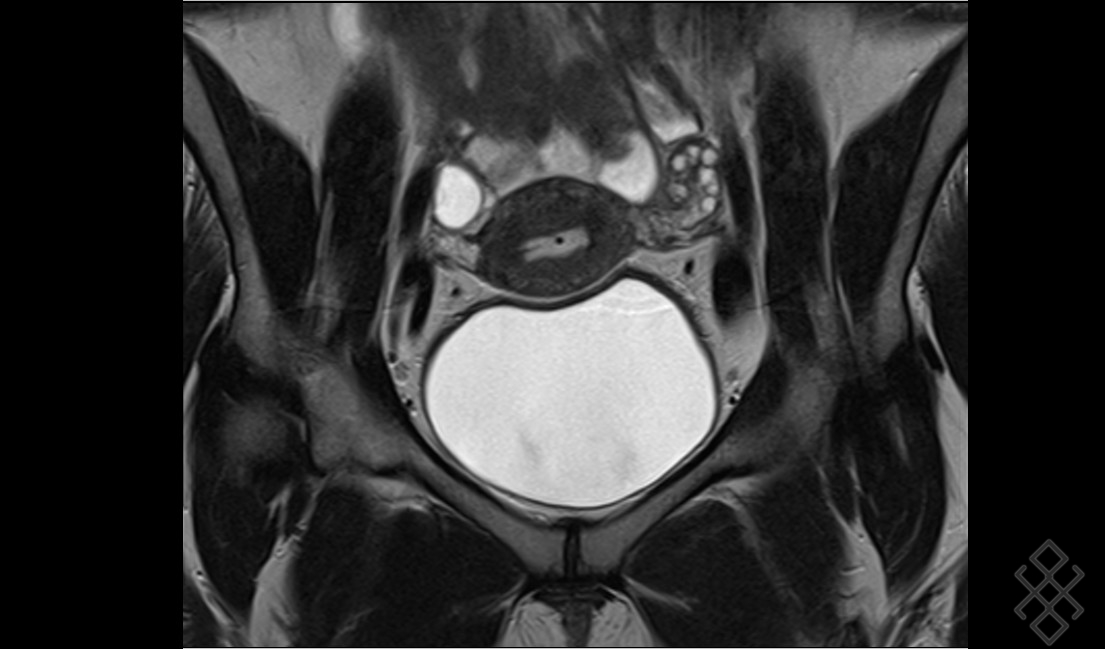

IRM pelvienne L'IRM est un examen non irradiant, sans risque, qui est très utile pour le diagnostic et le bilan d'une endométriose puis Comment se déroule l'examen IRM pelvienne dynamique ?

Dans la plupart des cas d'IRM pelvienne, vous devrez faire un lavement évacuateur quelques heures avant l'examen Comment faire un lavement Evacuateur ? Un lavement évacuateur consiste à injecter par l'anus un liquide dans le rectum ou l'extrémité du. Une préparation digestive par lavement rectal (Microlax) est recommandée afin d'améliorer la qualité des images.

PPT IRM PELVIENNE Pour les nuls PowerPoint Presentation ID5221314. Quels organes Voit-on sur un IRM pelvien ? Qu'est-ce qu'une IRM pelvienne Comment se préparer à une IRM pelvienne ? "En fonction de la demande faite par le médecin généraliste ou spécialiste, le radiologue décidera s'il est nécessaire d'effectuer un lavement évacuateur quelques heures avant l'examen, s'il faut être à jeun (généralement six heures avant l'examen) ou s'il faut avoir une vessie pleine ou vide", répond la spécialiste.